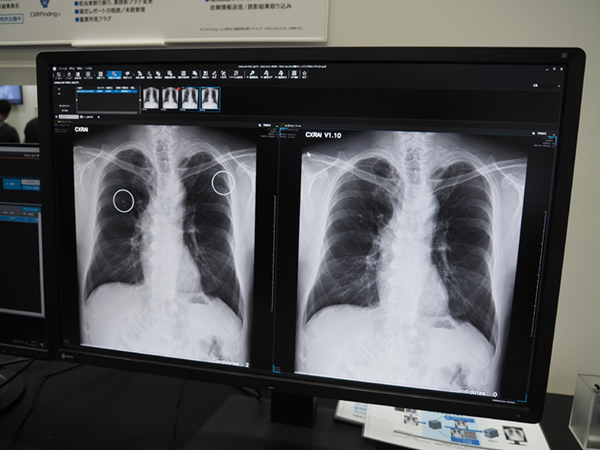

コニカミノルタグループのAIブランドであるFORXAIの下で展開する診断支援,業務支援などのAIが紹介された。そのうち胸部X線画像診断支援AIのCXR Finding-iは,胸部X線画像をAIで解析し,結節影や腫瘤影,浸潤影などの見落とし防止を支援するソフトウエア。感度向上に伴う偽陽性率の増加が課題の一つであったが,国内外で取得した数十万件以上の画像の学習(Deep Learning)により,感度を維持しつつ特異度を従来の69%から88%に大きく改善した。

胸部X線画像診断支援AI「CXR Finding-i」